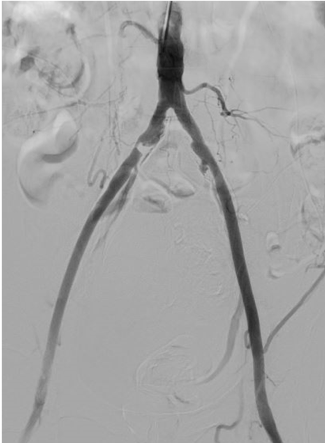

7.心血管造影検査

心血管造影装置

冠動脈造影検査(造影剤使用)

冠動脈内圧測定、血管内超音波検査、心筋生検なども可能です。

下肢動脈造影検査(造影剤使用)